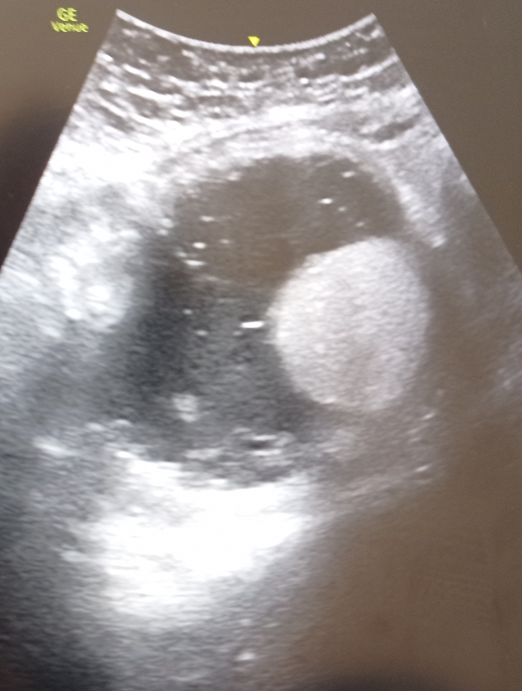

En urgencias, administramos analgesia de primer escalón. Tras 3 h de evolución, se decide realizar ecografía abdominal a pie de cama por persistencia del dolor viendo una imagen sugestiva de masa adyacente a ovario derecho que no conseguimos visualizar.

Tras realización de TAC abdominopélvico describen teratoma torsionado de ovario derecho.

Teratoma torsionado de ovario derecho.

La ecografía clínica en este caso, ayudó a buscar el origen del dolor en un abdomen agudo tras identificar una exploración ecográfica abdominal anormal y necesidad de ampliar el estudio.